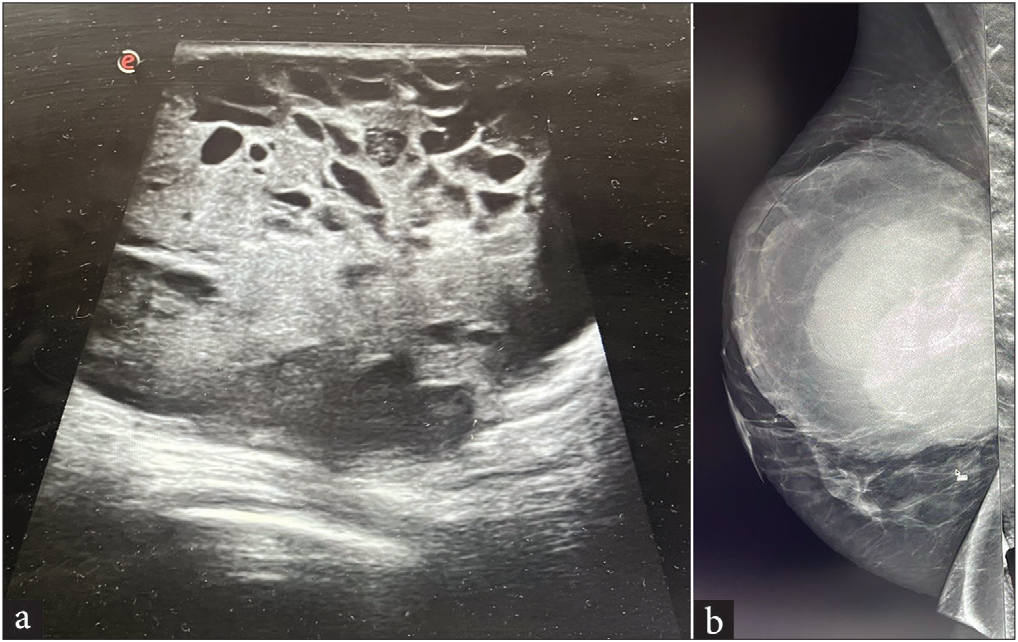

TNBC can present as a rounded circumscribed mass with posterior enhancement, which are features of benign tumors. Figure 5a shows a well-circumscribed solid cystic mass with posterior acoustic enhancement. BIRADS 4C category was assigned by USG on the basis of the sudden increase in size of the lesion and the presence of suspicious ipsilateral lymph nodes. The lesion came out to be invasive ductal carcinoma, grade 3, TNBC. Figure 6 shows a similar oval-shaped mass lesion with circumscribed margins, internal cystic spaces, and posterior enhancement. Due to the chronicity of the lesion and absence of suspicious lymph nodes, a BIRADS category of 4B was assigned on USG. The lesion turned out to be a benign phyllodes tumor on histopathological examination (HPE).

- A 25-year-old female presented with a rapidly growing lump in the right breast associated with pain. (a) A grayscale ultrasound of the right breast shows a large, rounded, circumscribed, solid-cystic mass with associated posterior enhancement. (b) The CC view of the mammography shows a large rounded high-density lesion with circumscribed margins occupying all quadrants of the breast. CC: Cranio-caudal.